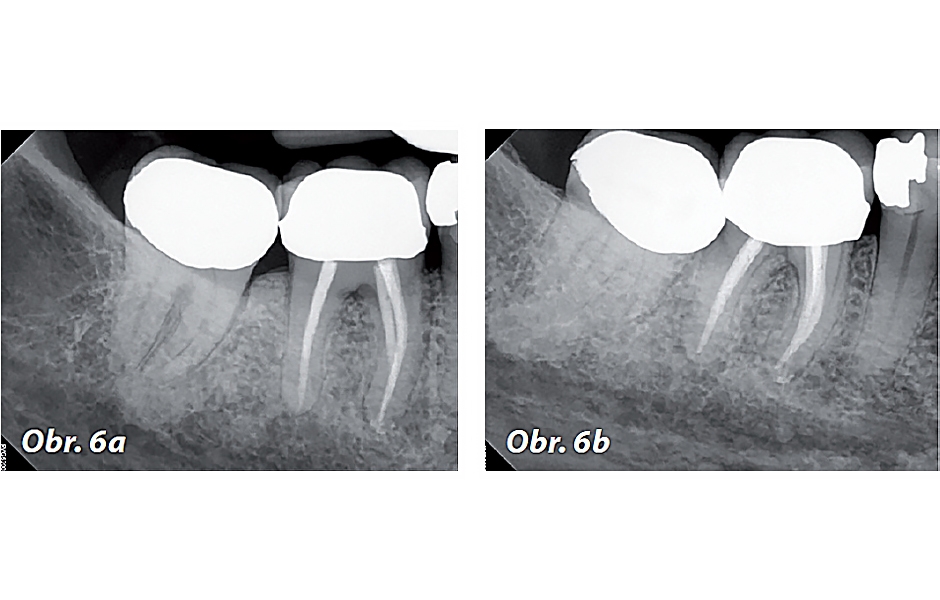

Kontrola po 12 měsících v červnu 2023: Pacientka byla asymptomatická a sondážní hloubky kolem zubu 46 byly < 4 mm. Zub 46 byl bez citlivosti na poklep a palpaci, s fyziologickou mobilitou. Pacientka souhlasila s pořízením PA rentgenových snímků (obr. 6 a, b) a CBCT skenu s omezeným zorným polem (obr. 7 a–c). PA snímky vykazují známky hojení v oblasti meziálních i distálních apexů.

CBCT sken (obr. 7a) ukazuje zaplnění středního meziálního kanálku a konvergenci distobukálního (DB) a distolingválního (DL) kanálku. Koronální řezy meziálního a distálního kořene (obr. 7 b–c) potvrzují apikální hojení obou kořenů. Klinické a radiografické nálezy indikují, že zub 46 je zhojen. Další kontrola není nutná, pokud pacientka nebo její zubní lékař nezaznamenají změny v klinických či radiografických příznacích.

Obr. 6a, b: Kontrolní PA rentgenové snímky zubu 46 v červnu roku 2023.

Obr. 7a–c: Kontrolní CBCT řezy zubu 46 – a) axiální, b) meziální kořen, c) distální kořen.